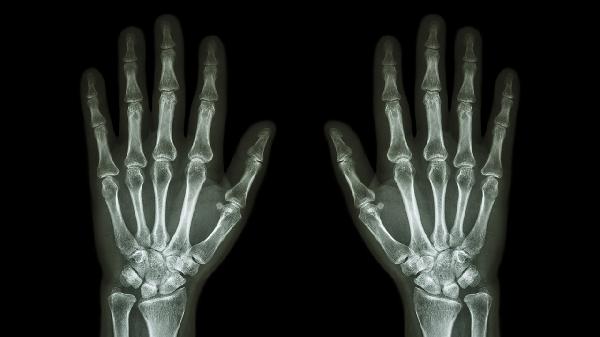

脱臼关节会出现明显变形,指节可能呈现异常弯曲或缩短。由于关节面完全脱离正常位置,手指轴线发生改变,可能出现侧方移位或旋转畸形。肉眼可见的畸形是临床诊断的重要依据,须通过X光检查确认是否合并撕脱性骨折。